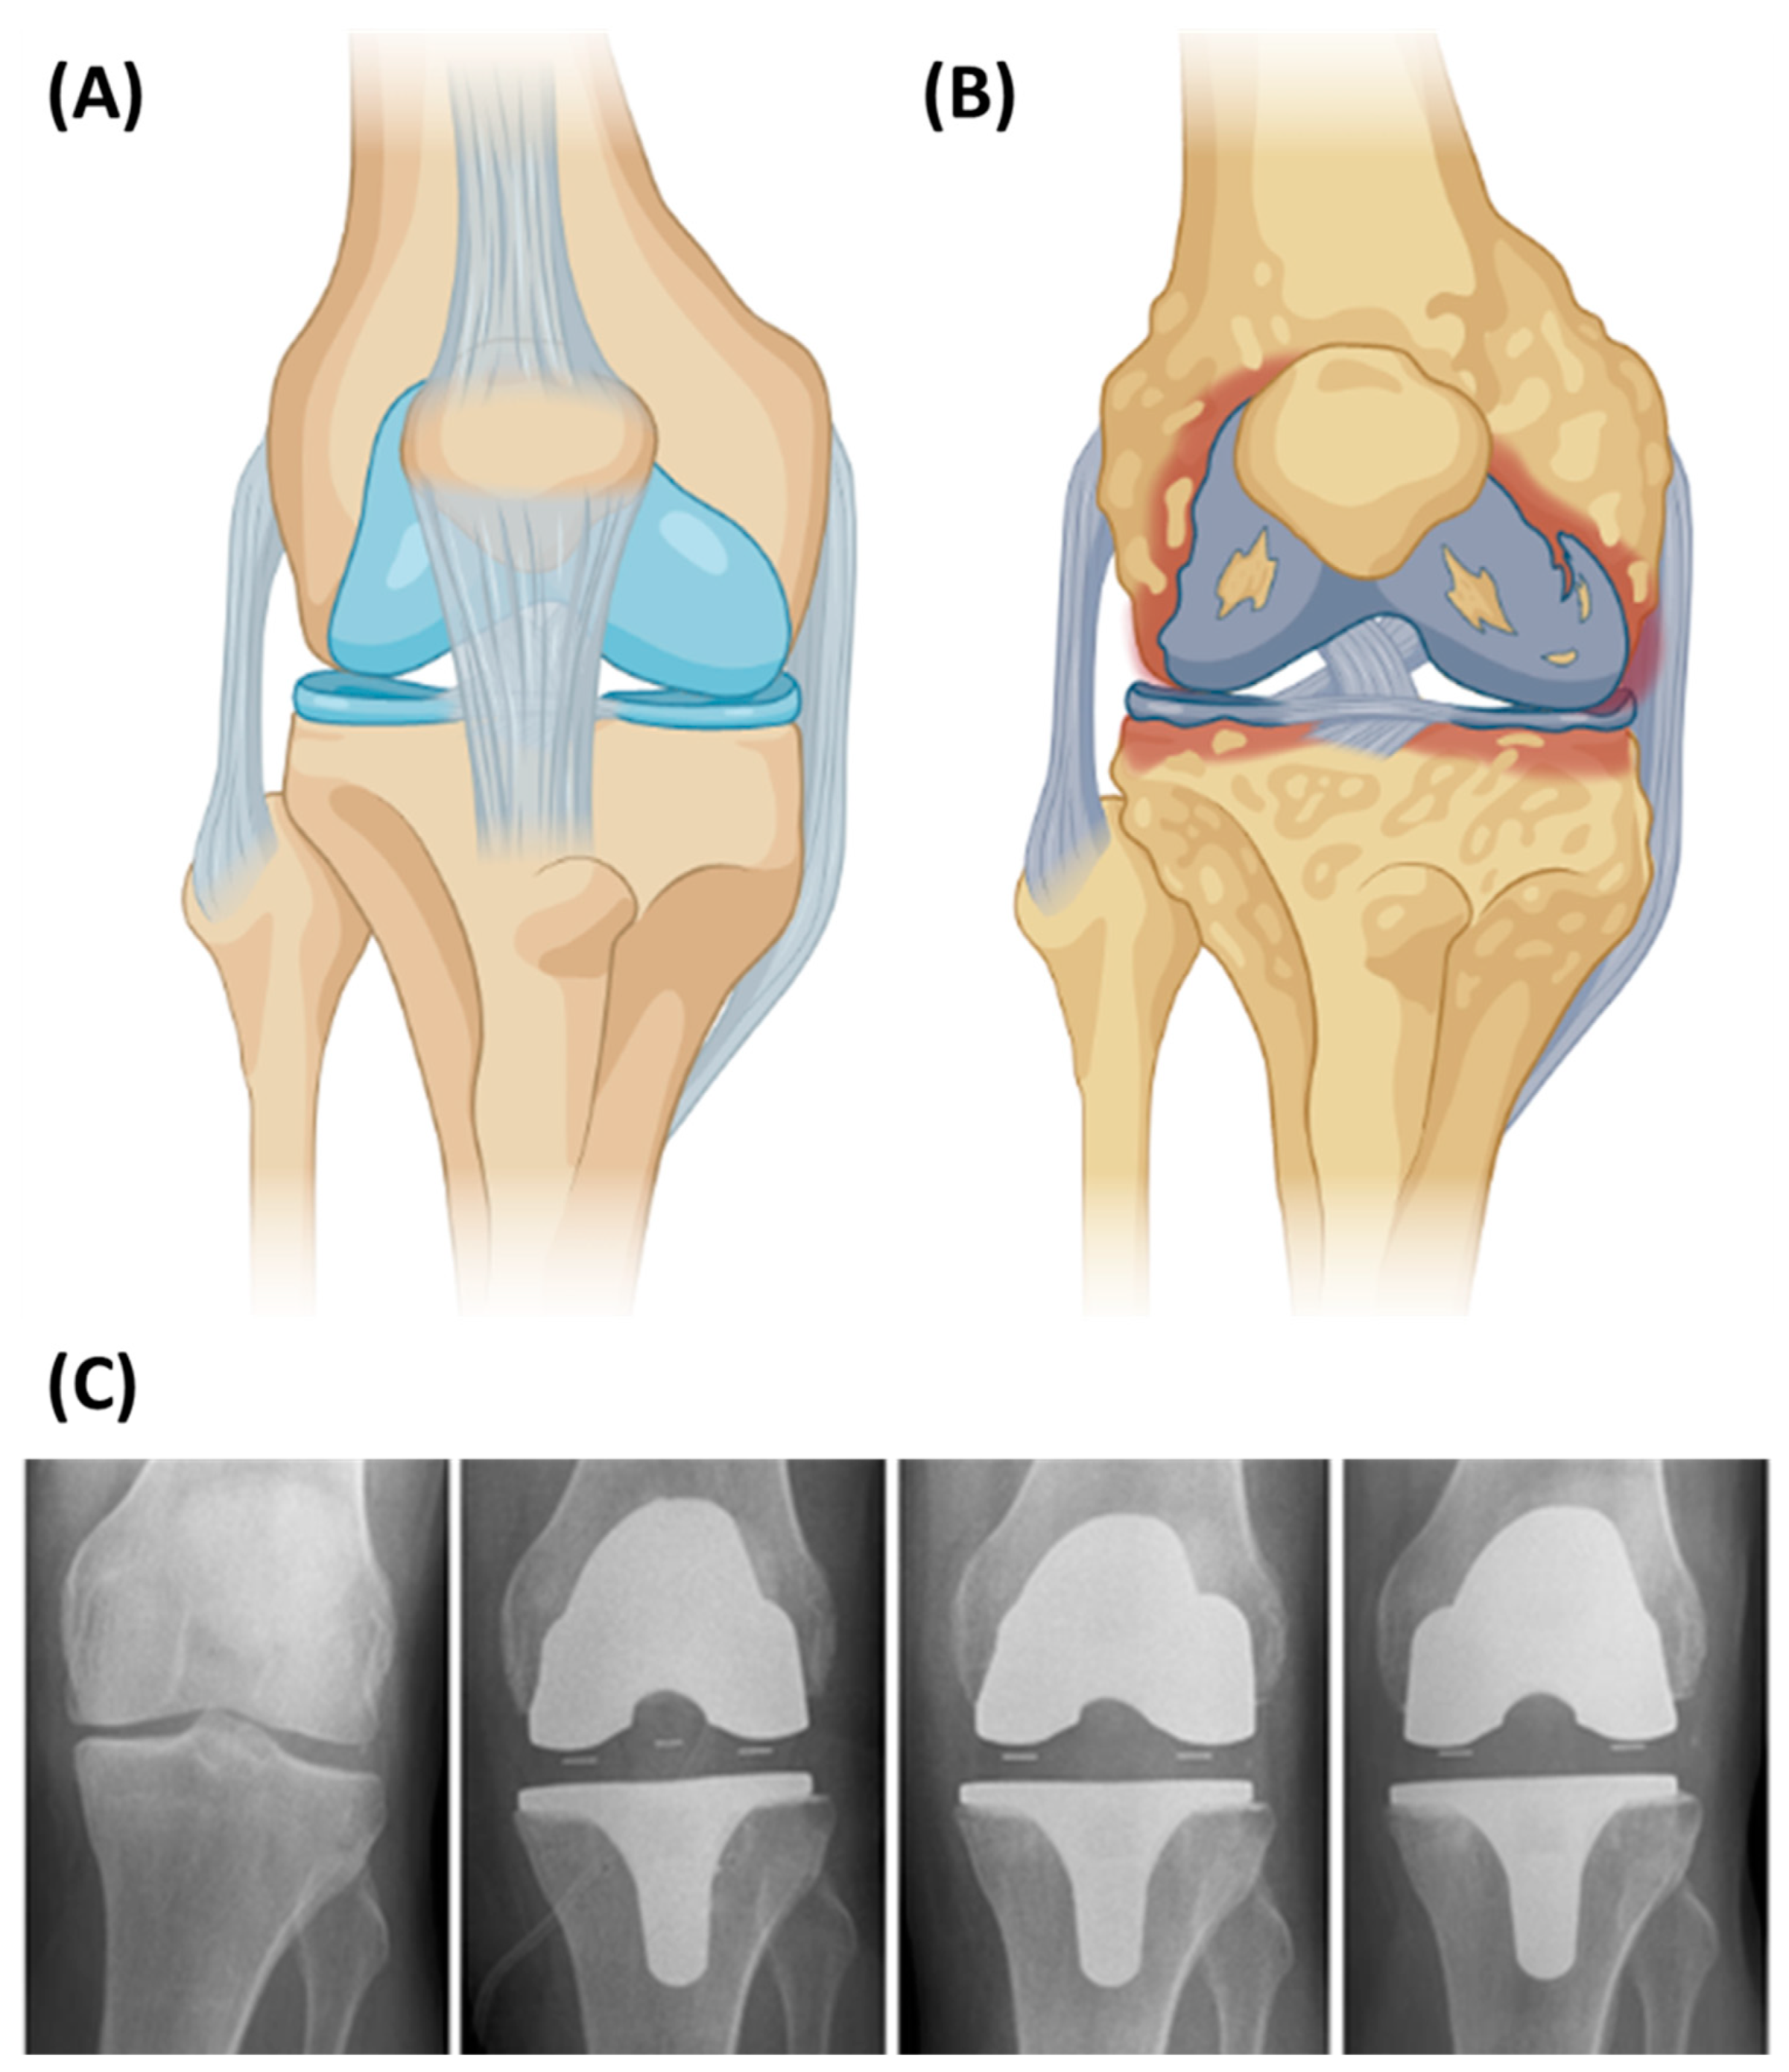

5.3. Knee Implants

- Nakamura, S.; Ito, H.; Nakamura, K.; Kuriyama, S.; Furu, M.; Matsuda, S. Long-Term Durability of Ceramic Tri-Condylar Knee Implants: A Minimum 15-Year Follow-Up. J. Arthroplasty 2017, 32, 1874–1879. [Google Scholar] [CrossRef] [PubMed]

- Nakamura, S.; Kobayashi, M.; Ito, H.; Nakamura, K.; Ueo, T.; Nakamura, T. The Bi-Surface total knee arthroplasty: Minimum 10-year follow-up study. Knee 2010, 17, 274–278. [Google Scholar] [CrossRef] [PubMed]

- Bergschmidt, P.; Bader, R.; Ganzer, D.; Hauzeur, C.; Lohmann, C.H.; Krüger, A.; Rüther, W.; Tigani, D.; Rani, N.; Esteve, J.L.; et al. Prospective multi-centre study on a composite ceramic femoral component in total knee arthroplasty: Five-year clinical and radiological outcomes. Knee 2015, 22, 186–191. [Google Scholar] [CrossRef] [PubMed]

- Meier, E.; Gelse, K.; Trieb, K.; Pachowsky, M.; Hennig, F.F.; Mauerer, A. First clinical study of a novel complete metal-free ceramic total knee replacement system. J. Orthop. Surg. Res. 2016, 11, 1–7. [Google Scholar] [CrossRef] [PubMed]

- Brehm, P. BPK-S INTEGRATION Ceramic Knee Prosthesis. Available online: https://www.peter-brehm.de/en/products/knee/bpk-s-integration/ (accessed on 5 September 2022).